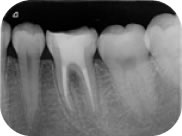

生活歯髄療法

生活歯髄療法とは、歯の中の神経(歯髄)を全部または一部保存する治療法のことです。

食事をすると痛い、しみるといった症状があっても、歯髄が正常な場合に選択される治療法です。

従来、歯髄を残す治療には水酸化カルシウムによる直接覆髄法が多く用いられてきました。しかし水酸化カルシウムによる処置は成功率が低く、結果的に神経を取る処置必要になることも多くありました。

髙橋歯科では、ケイ酸カルシウムを主成分としたMTAによる覆髄治療を行っております。

MTAを使うことによって、従来の水酸化カルシウムセメントによる治療と比べて、高い確率で歯髄を保存することが可能となっています。